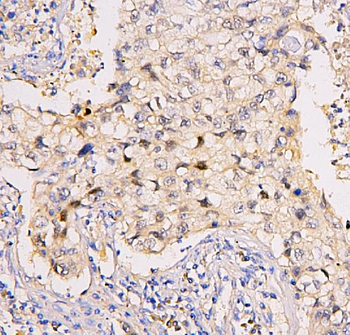

Immunohistochemistry of paraffin-embedded human colon using orb631314 (SMARCA4 Antibody) at dilution of 1:50.